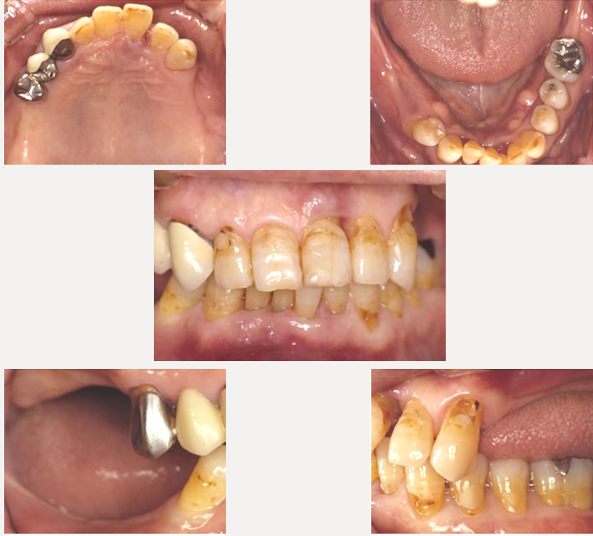

治療前

左右の奥歯がなく前歯だけで噛んでいました。その為に歯周病が進行し前歯が動いてきています。レントゲンで細かく検査すると、残っている歯も歯周病が進行していました。噛み合わせも含めた総合治療が必要でした。